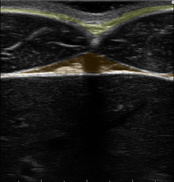

みぞおちに当てて出てくる画像のパターンによって、その人の「これまでの生活習慣」と「今後改善しなければならないこと」が分かります。

【理想的パターン】

【過剰な食べ過ぎと筋トレ不足パターン】

【隠れ肥満(食べ過ぎ)パターン】

【砂糖の過剰摂取と有酸素運動不足パターン】